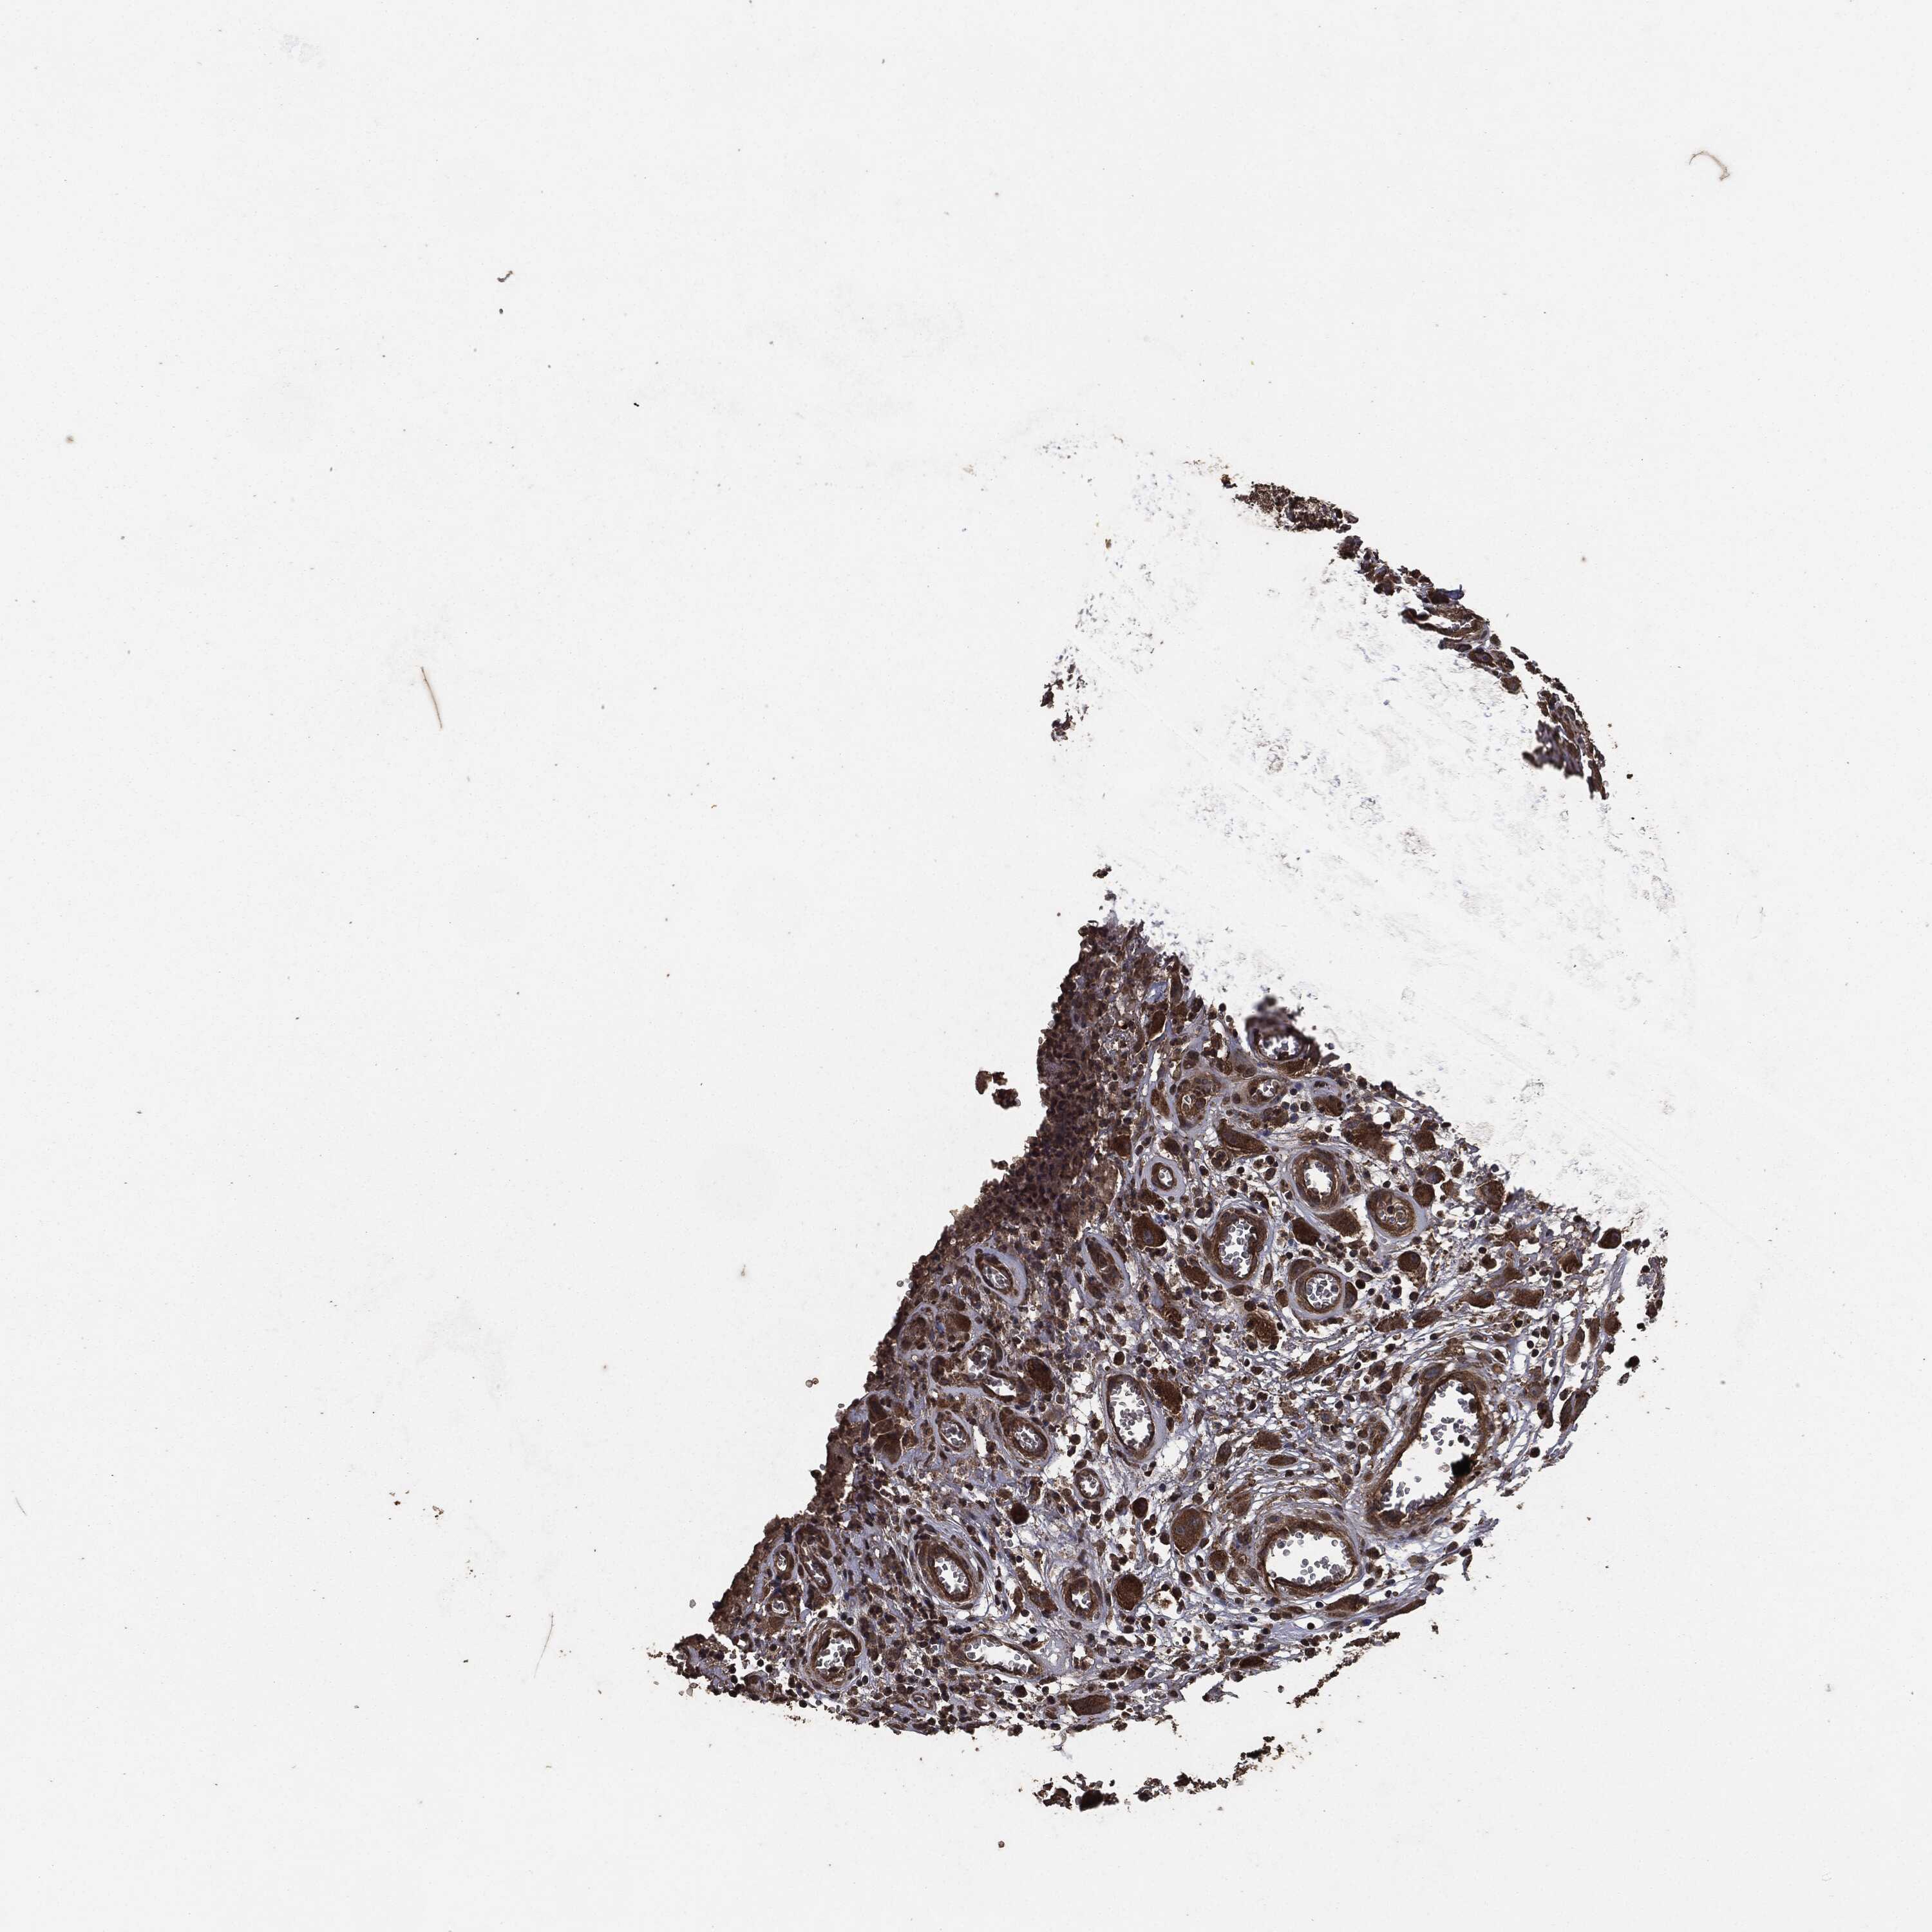

HEAD AND NECK CANCER - Protein expressioni

A mouse-over function shows sample information and annotation data. Click on an image to view it in a full screen mode. Samples can be filtered based on level of antibody staining by selecting one or several of the following categories: high, medium, low and not detected. The assay and annotation is described here.

Antibody stainingi

Antibody staining in the annotated cell types in the current human tissue is reported as not detected, low, medium, or high, based on conventional immunohistochemistry profiling in selected tissues. This score is based on the combination of the staining intensity and fraction of stained cells.

Each image is clickable and will lead to virtual microscopy that enables deeper exploration of all samples and also displays staining intensity scores, fraction scores and subcellular localization as well as patient and tissue information for each sample.

Antibody HPA064427

Antibody HPA075510

Antibody CAB021903

Staining

High

Medium

Low

Not detected

Intensity

Strong

Moderate

Weak

Negative

Quantity

>75%

75%-25%

<25%

None

Location

Nuclear

Cytoplasmic/membranous

Cytoplasmic/membranous,nuclear

Squamous cell carcinoma, NOS

Adenocarcinoma, NOS

Squamous cell carcinoma, metastatic, NOS

Adenoma, NOS